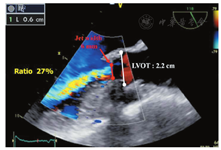

1. 彩色多普勒评价

2. 综合评价

应用彩色多普勒血流可从多个切面观察舒张期流入LV的主动脉瓣反流束。早期研究对AR严重程度的界定多集中在对彩色血流束的特征性描述方面[14,20]。由于血流动力学状态、仪器设置、接受反流的心腔特点、偏心性射流、射流束冲击心腔壁的差异以及来自阅图者的差异,利用反流束的面积和长度判断反流严重程度的方法存在明显的局限性[140]。鉴于彩色反流束的面积和长度与人工瓣AR的程度相关性较差,因此不推荐用于人工瓣AR的定量评价[20]。胸骨旁长轴切面测量的反流束直径/LVOT直径,以及胸骨旁短轴切面贴近人工瓣膜下方测量的反流束面积/LVOT面积,可用来评价中央性反流的严重程度(图11)。反流束直径/LVOT直径>65%提示为重度反流[141]。然而,该方法在偏心性或新月形反流的情况下可能高估反流的严重程度,而在反流束冲击LVOT壁或二尖瓣前叶的情况下可能低估反流严重程度。

对瓣周性AR的半定量评价,需在缝合环水平的短轴切面仔细显示射流束的颈部,以精确定义其周向范围,可用反流束周长占整个缝合环周长的百分比表示反流的严重程度(<10%为轻度,10%~29%为中度,≥30%为重度)(图16)[14,125,142]。然而,这一方法受偏心性反流方向和反流束形状不规则的限制。人工瓣膜的摇摆运动常常提示瓣环开裂>40%,并造成重度反流[143]。在多个切面上观察瓣周反流起始部的宽度也有助于评价反流程度。

由于人工瓣环或支架造成的强回声声影,缩流束宽度(反流束穿过主动脉瓣口的宽度或有效反流面积)在长轴切面上难以正确测量,而在存在多个反流束、反流口形状不规则或瓣周反流的径向扩展等情况下,其测量是不准确的[64]。测量缩流束宽度有助于区分轻度和重度的人工瓣AR。采用Nyquist极限50~60 cm/s时,缩流束宽度<3 mm为轻度AR,而缩流束宽度>6 mm则提示为重度AR。